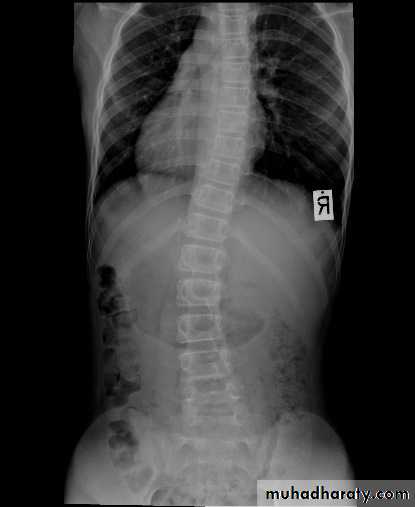

DEFORMITIES

Scoliosis